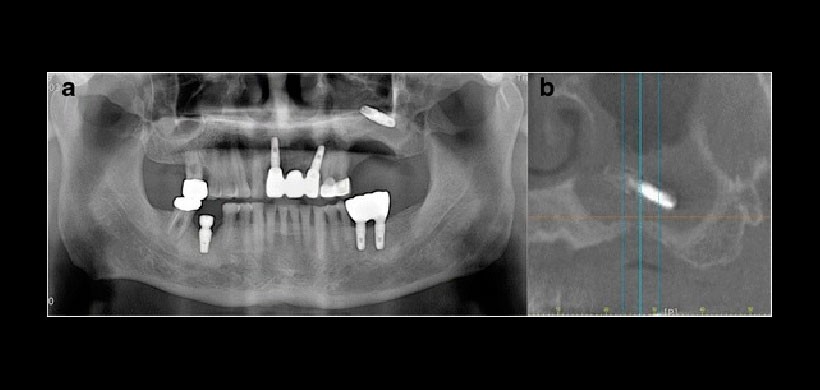

Figura 1: a) Vista panorámica preoperatoria y b) Vista de la tomografía computarizada cone beam (CBCT)